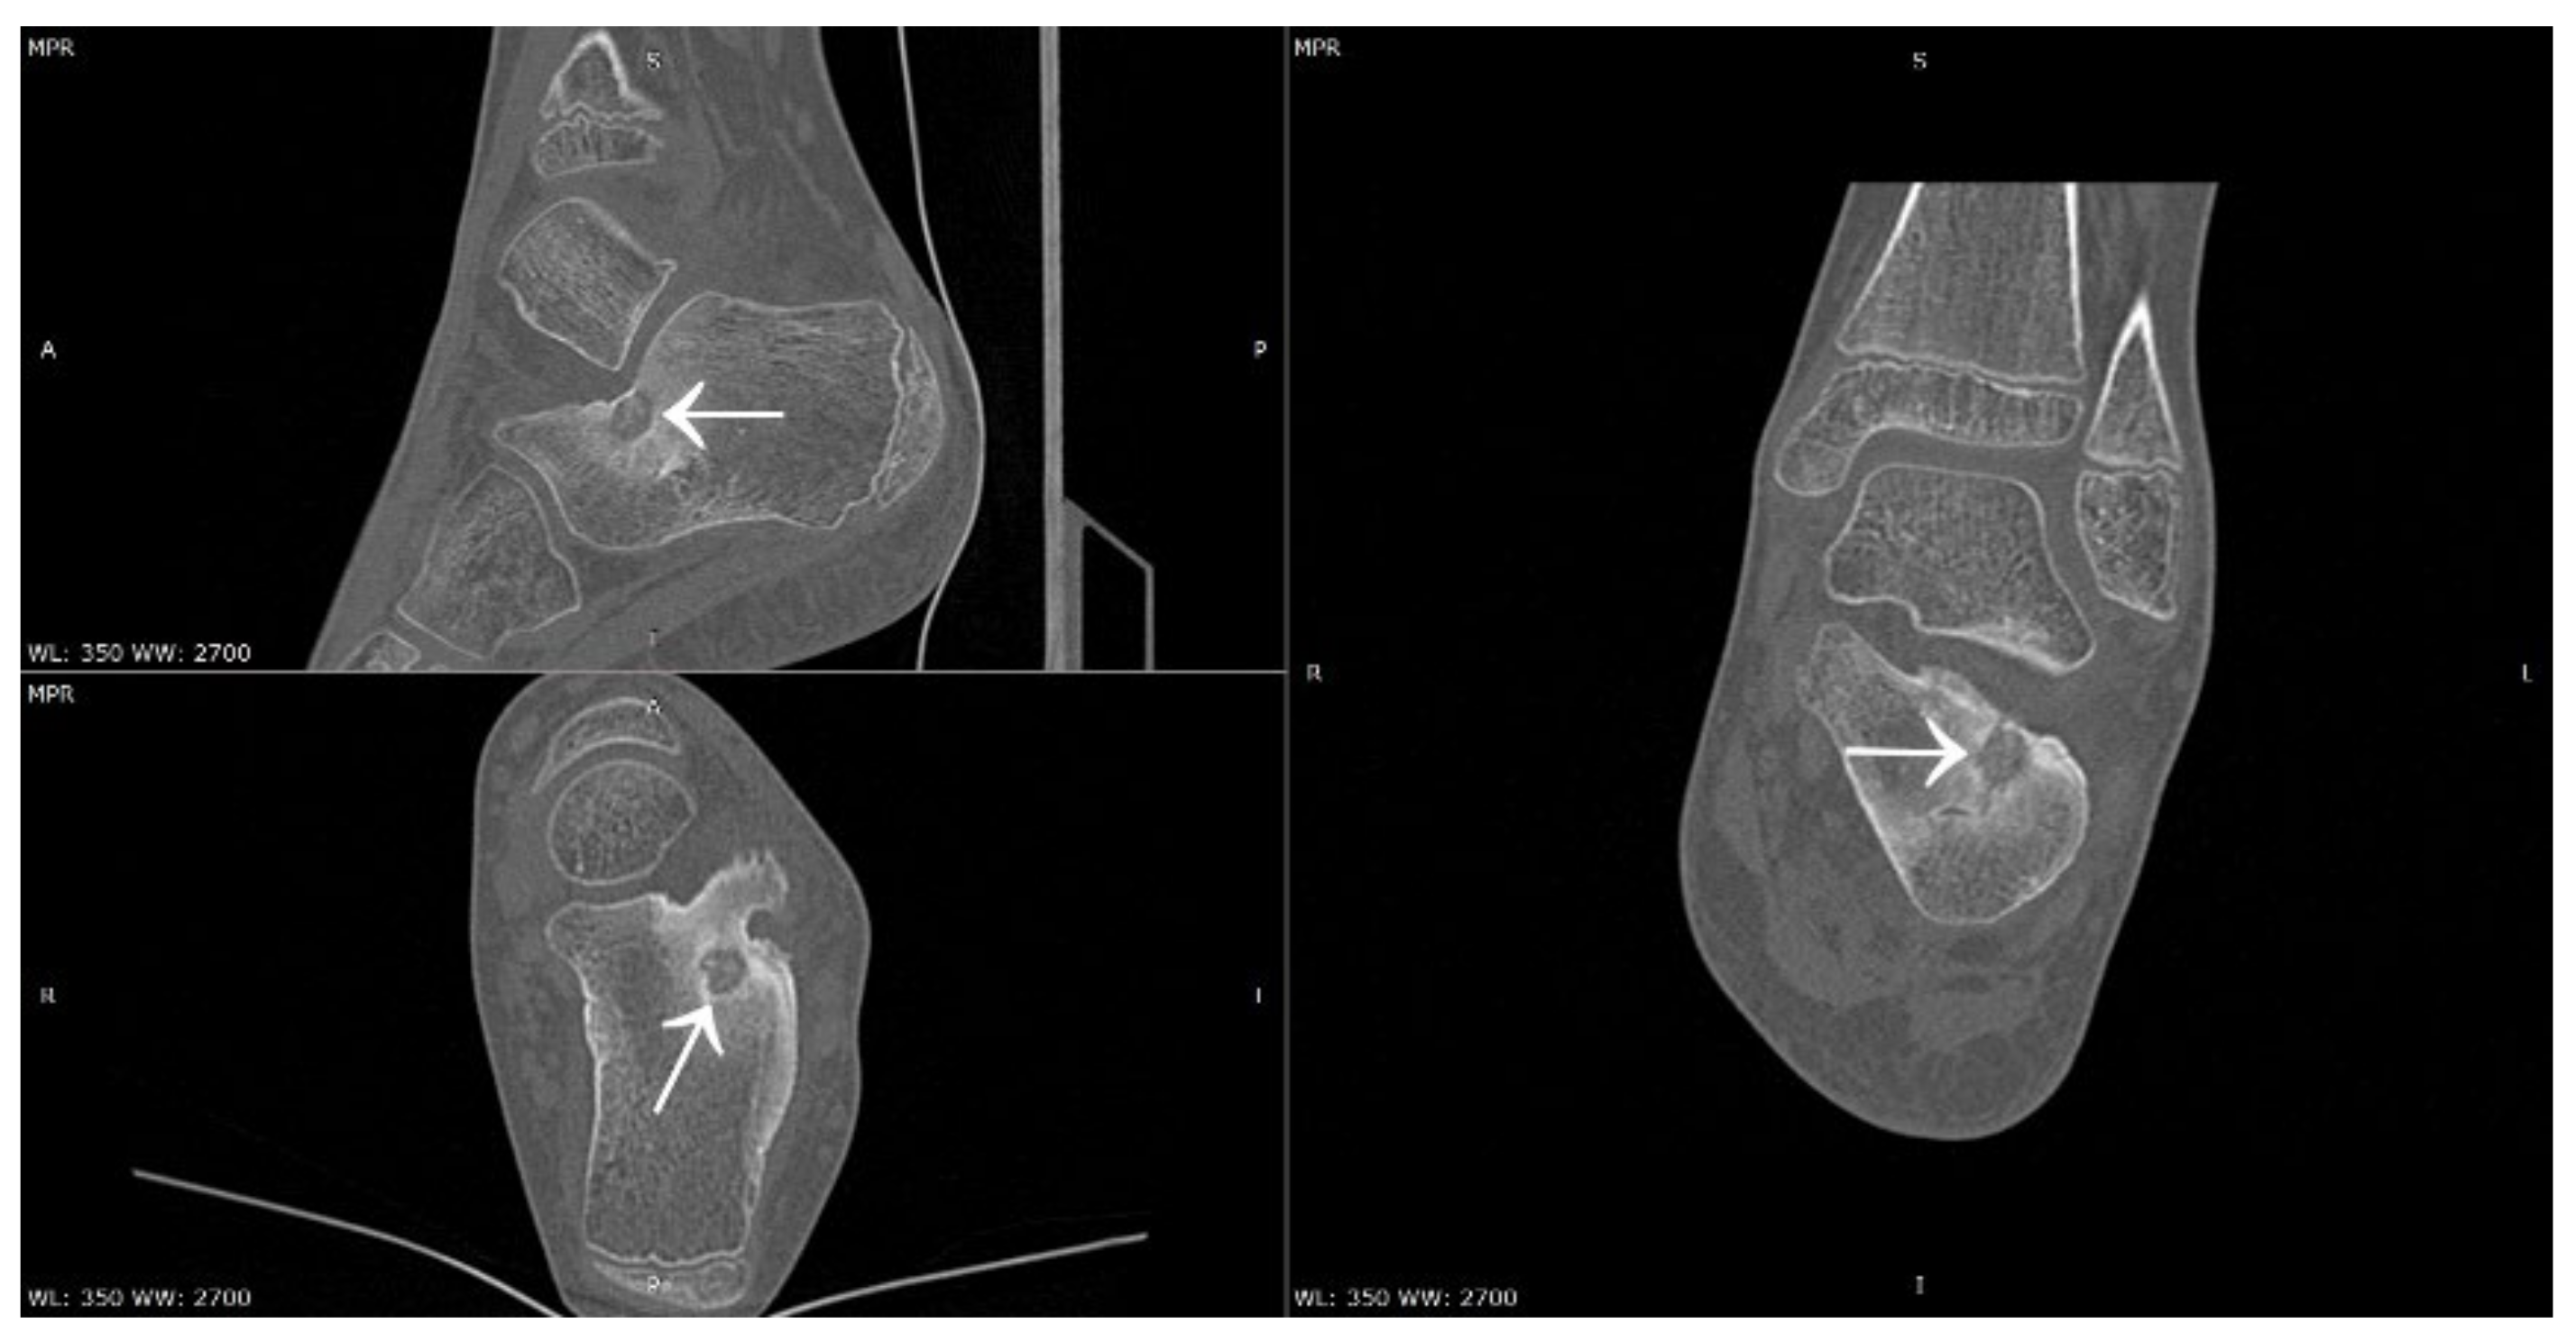

Figure 17.

CT scans showing a focus of OO (arrows) in the left calcaneus.